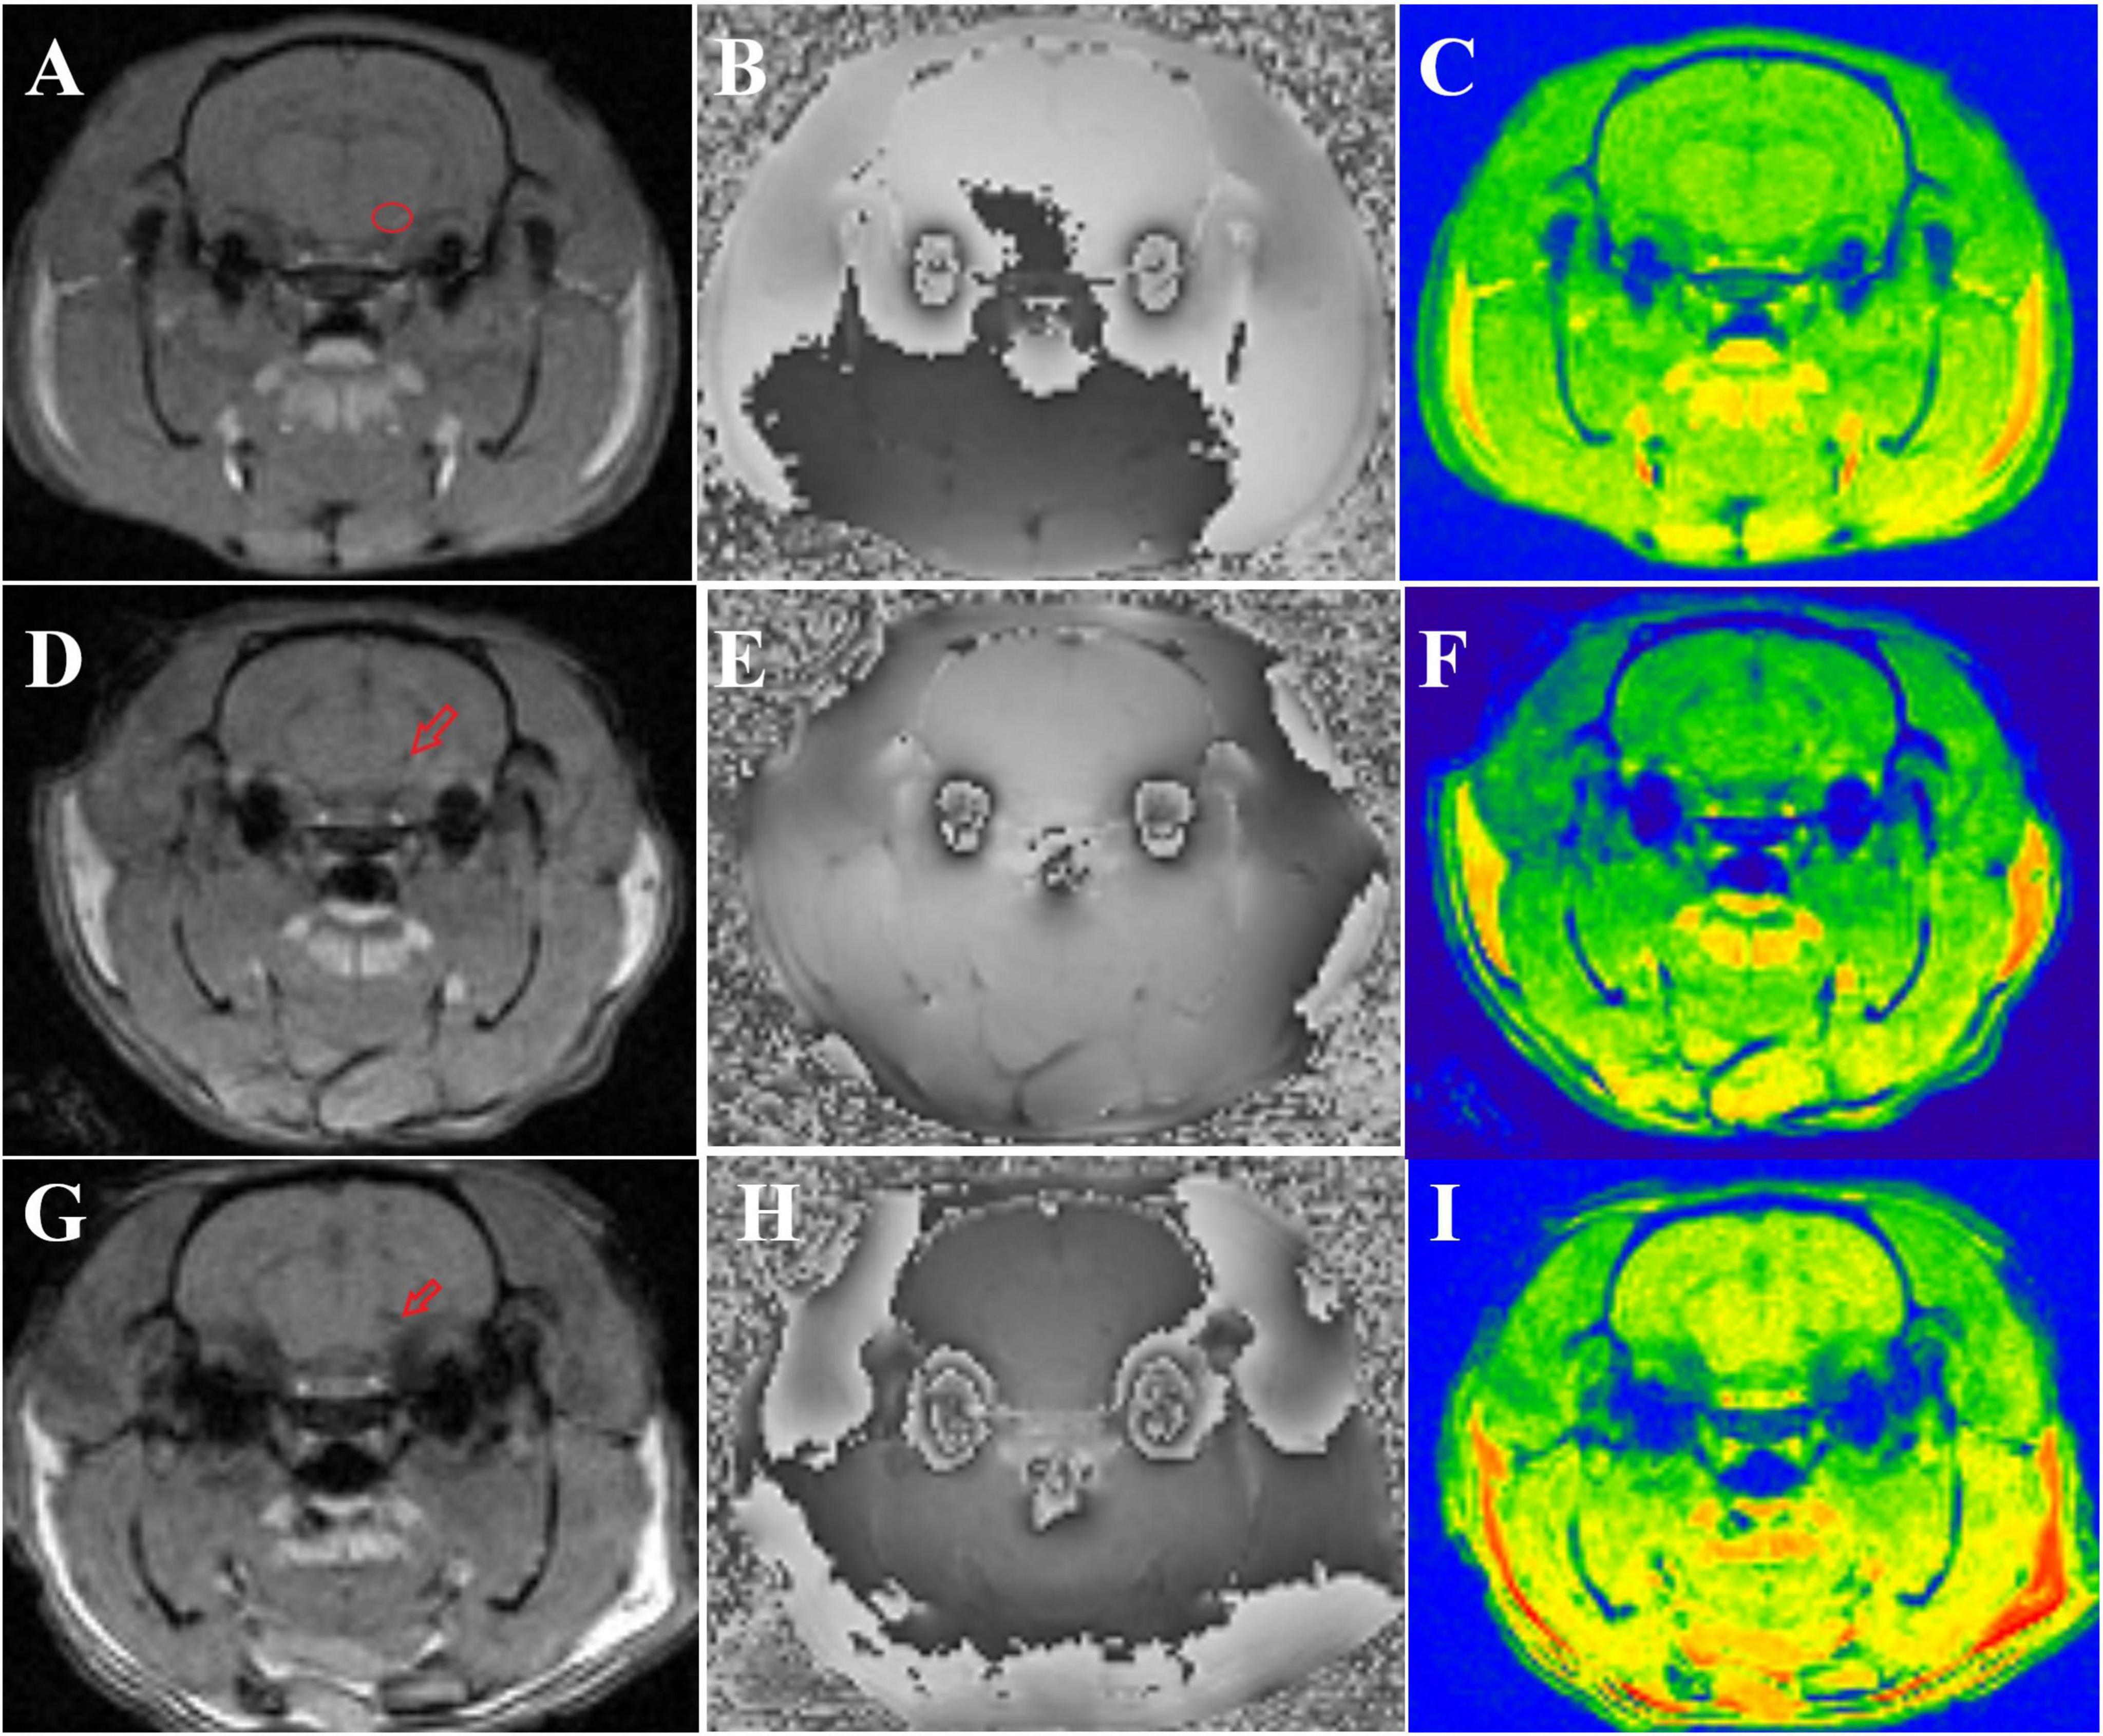

There were no significant differences in the magnitude or R2* values among the three groups of rats before modeling (p > 0.05), see Table 1 for details. At 6th week, the results showed significant statistical differences in the magnitude values and R2* in the right SN region among the three groups of rats (magnitude: F = 82.46, p < 0.0001; R2*: F = 205.00, p < 0.0001). Specifically, the magnitude values in the right SN region of the treatment group were significantly higher than those in the PD group (p < 0.0001), whereas the R2* values were significantly lower (p < 0.0001), suggesting a reduction in susceptibility in the right SN region after probiotic treatment. However, the magnitude values in the treatment group remained lower than those in the control group (p = 0.0002), and the R2* values were significantly higher (p < 0.0001), indicating that even with active probiotic treatment, the brain state might not fully return to that of the unmodeled rats (Figure 1). The magnetic resonance images of the SN level in the brains of the three groups of rats are shown in Figure 2.

Figure 2. Shows the magnetic resonance images of three groups of rats. (A–C) Display the magnitude, phase, and R2* map of control group rats, respectively. The small red circle in panel (A) indicates the location of the ROI outlined in the right SN. (D–F) show the magnitude, phase, and R2* map of treatment group rats, respectively, with the small red arrow in panel (D) indicating iron deposition in the right SN. (G–I) present the magnitude, phase, and R2* map of PD group rats, respectively, and the small red arrow in panel (G) denotes iron deposition in the right SN.